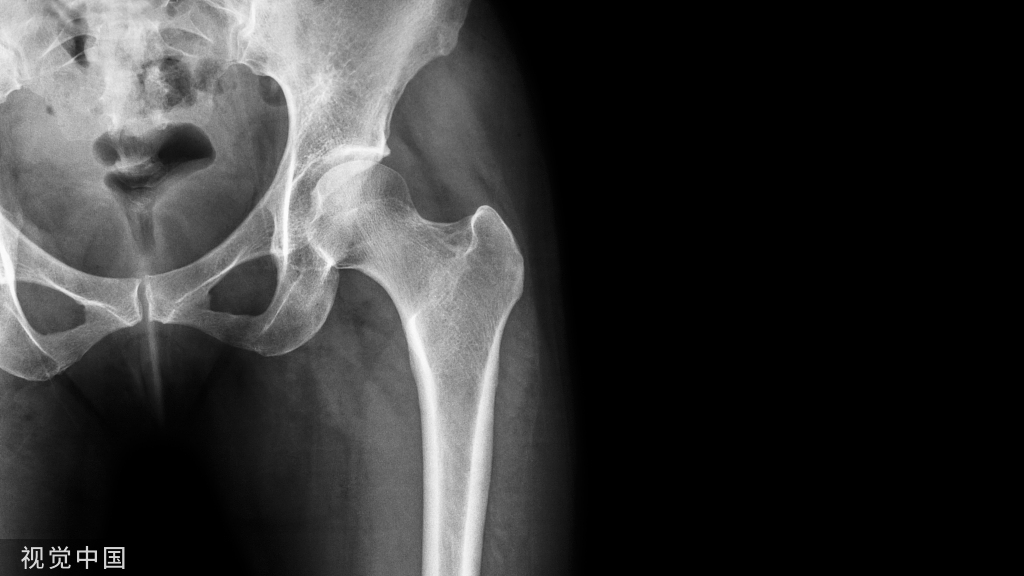

粗隆间骨折是致死率很高的手术,近年来粗隆间的并发症越来越多。